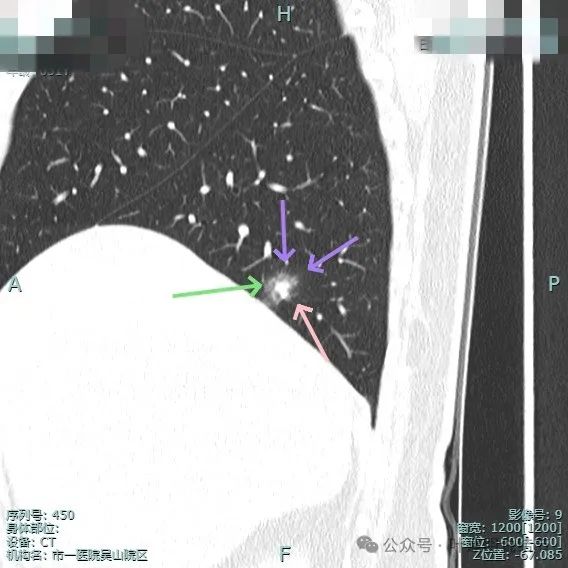

再看在我门诊时2025年1月14号复查的靶扫描影像:

明显的血管进入与异常增粗。

血管进入与异常增粗并散开来(在肿瘤性病变中,这种表现是浸润性而且风险大的表现)。

血管进入穿行并异常增粗,磨玻璃成分显得较为散在,缺乏聚拢性。